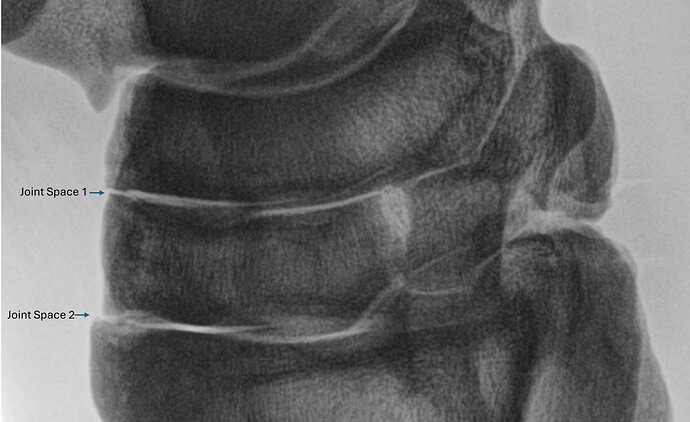

Hello everyone. I hope this is the correct forum for this question. I am a veterinary orthopedic researcher. We have x-ray images (like the one below) and are trying to measure the amount of joint space (white regions) relative to the overall dark (bone) in these images. Is there a way - in GIMP or elsewhere, where the program can “look” at the image, subtract the “white” from the rest of the image and give me an objective number (X pixels or Y ) of white versus black ? Additionally, if I can tell that the first joint space (labelled 1 in the image) contributes z of the overall “white areas” and the second space (labelled 2) contribute z1% that would be amazing. We are not trying to manipulate images for publication. We are trying to get objective numbers to allow us to run statistical comparisons.